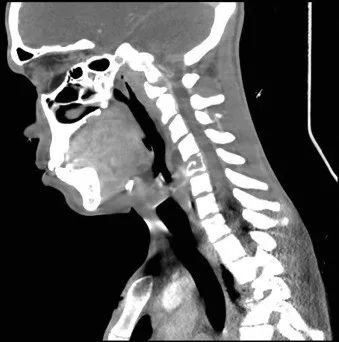

全血白细胞计数为13.4*109/L,血红蛋白8.5g/dL,血小板138/μL,C-反应蛋白28.8(正常值<3.0)。动脉血气分析显示pH值为7.30,PCO2为48.2,PO2为71.8,血培养呈阴性,进行BAL培养(包括细菌培养、病毒培养、真菌培养)。胸部X线及胸部CT显示弥漫性斑片状阴影(图1.2)。颈椎、胸椎和腰椎的CT扫描显示椎体病变(图3.4)。由于脾脏有多处病变,也进行了脾活检(图5)。

图3 颈椎/胸椎CT:C5椎体广泛透明、前路高度破坏约70%

图4 腰椎CT:T11和L2椎体破坏性病变